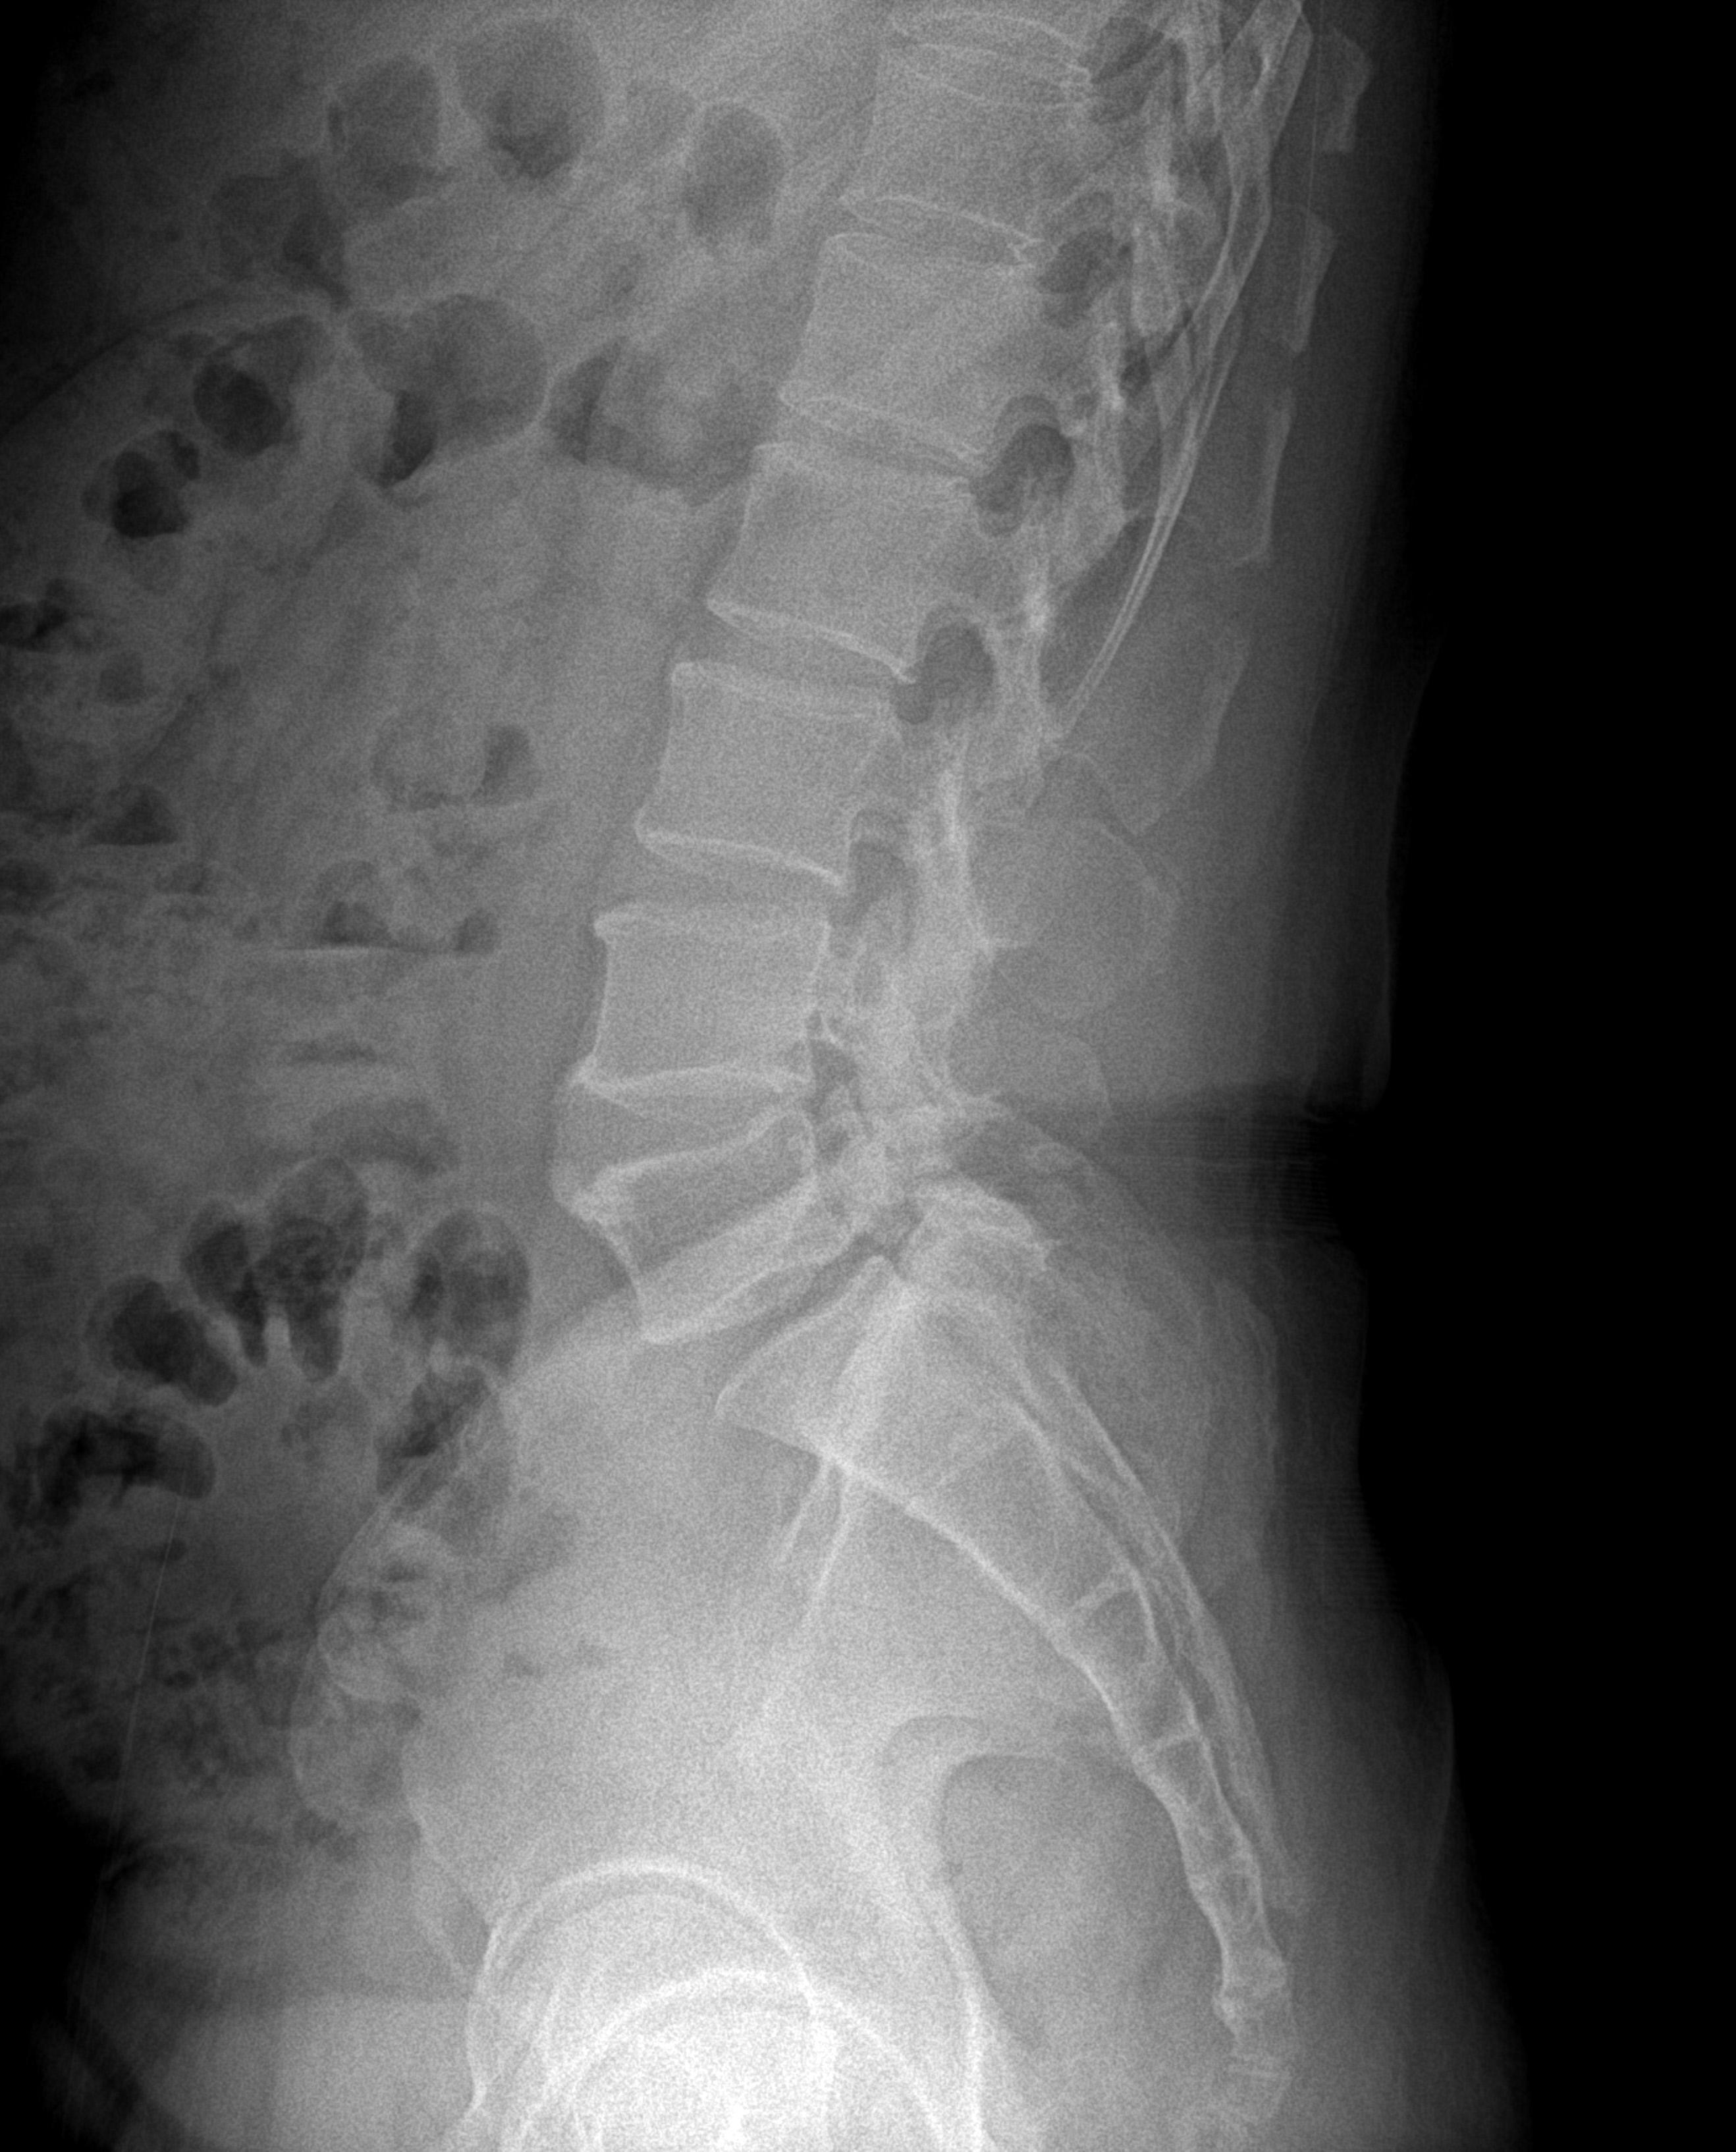

사랑의교회 제적이 10만명으로 추산하니까 그중에 정형외과 의사께서 아래 X-Ray 를 보시면 걸어다니기 힘들다는 것을 아실 것이다. 그런데 主께서 고쳐주셔서 나이 50의 고비를 넘겼다. 오늘 쥬빌리 통일 구국 기도회에 가면, 공부를 못하게 되는데 내일 새벽기도회도 문제다.